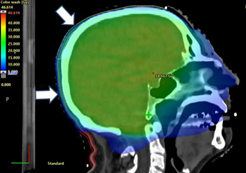

A 71-year old Caucasian male with metastatic melanoma required whole brain radiotherapy (WBRT). He was initially on combination immunotherapy with nivolumab and ipilimumab which was changed two months after WBRT to single agent nivolumab. He was treated with a hair-sparing protocol.9 The trial specific prescription delivered 30 Gy in 10 fractions to the whole brain as well as 40 Gy in 10 fractions via a SIB technique to two MRI detected asymptomatic brain metastases. The study delivered a lower dose to contoured superior (supscalp) and inferior (infscalp) scalp regions to try to spare scalp hair. The trial specific inferior scalp region (“inf scalp”) was a volume that included a hair bearing region that extended from a line 2 cm above the pinna to the hair line at the nape of the neck. The patient remained on nivolumab and 7.5mg of daily prednisolone throughout WBRT treatment. Figure 5 shows the hair colour prior to therapy. The original “inf scalp” volume (Figure 5B) received a maximum of 21 Gy, a minimum of 0.5 Gy and a mean dose of 11.7 Gy. One month post treatment, there was no change in hair colour but epilation in-field was apparent (Figure 5C). Hair below the arrows is the patient’s original hair colour prior to WBRT which retained its colour. At four months post WBRT, there was depigmentation of both the sup and inf scalp volumes. In order to be more precise about the hair colour change inferiorly, a new contour was created called “new infscalp”. This contour replicated the infscalp volume except that the lower border was on the line of the hair colour change, aligning it to the end of the WBRT field (Figure 5D). The dose was then recalculated from the original plan and a new dose volume histogram was produced (Figure 5F). The new “infscalp” volume (Figure 5B) received a maximum of 21 Gy, a minimum of 5 Gy and mean dose of 15 Gy (Table 2). Dosimetry of penumbral areas where the hair colour change was noted is detailed in Table 2.

Figure 5B Dosimetry on the midline sagittal planning scan from dose wash of 15 Gy of the Hair Spare protocol.9 Note the white arrow showing the trial specific infscalp volume which goes inferiorly to the hair line at the nape of the neck.

Figure 5E Dosimetry on the midline sagittal planning scan from dose wash of 5 Gy of the Hair Spare protocol. Note the diagonal white arrow showing the trial specific supscalp volume. The horizontal white arrow shows the new infscalp volume which goes inferiorly only to the level of the change in hair colour.